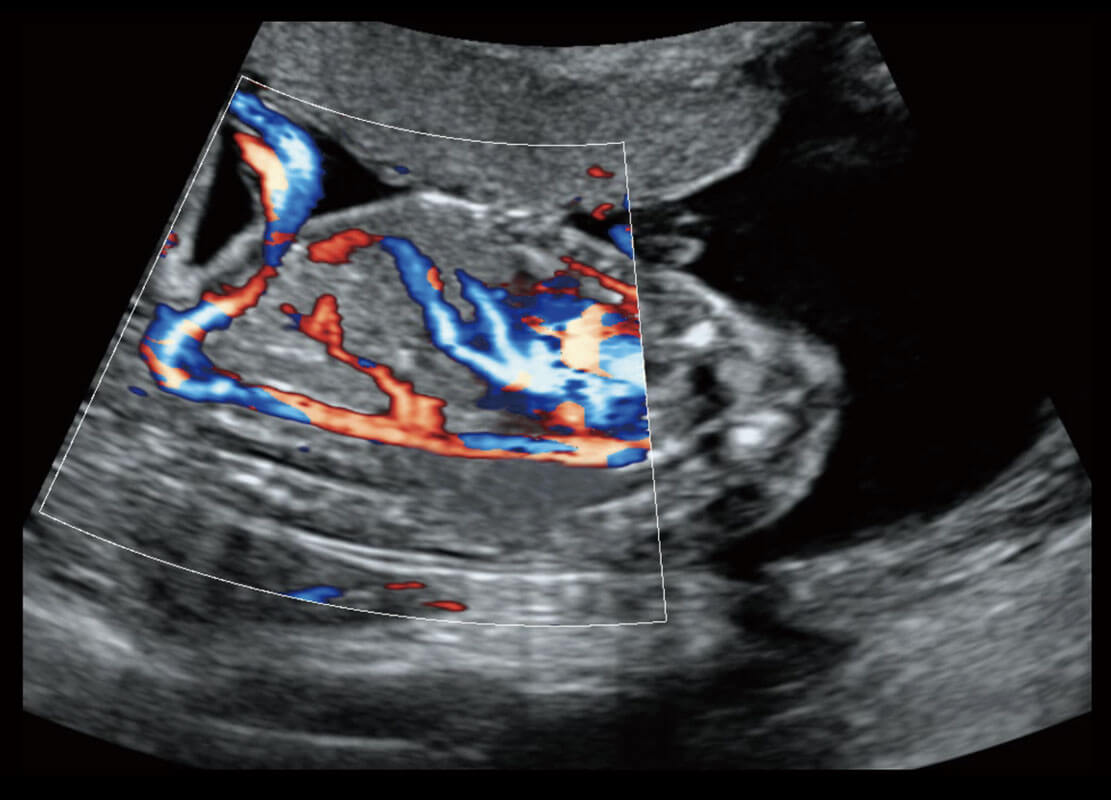

早孕筛查

P60在胎儿早孕期超声筛查中为您带来优异的图像质量。

• 早孕-胎心

• 高分辨率容积成像-早孕胎儿

• 胎儿体循环

• 光影成像-孕囊